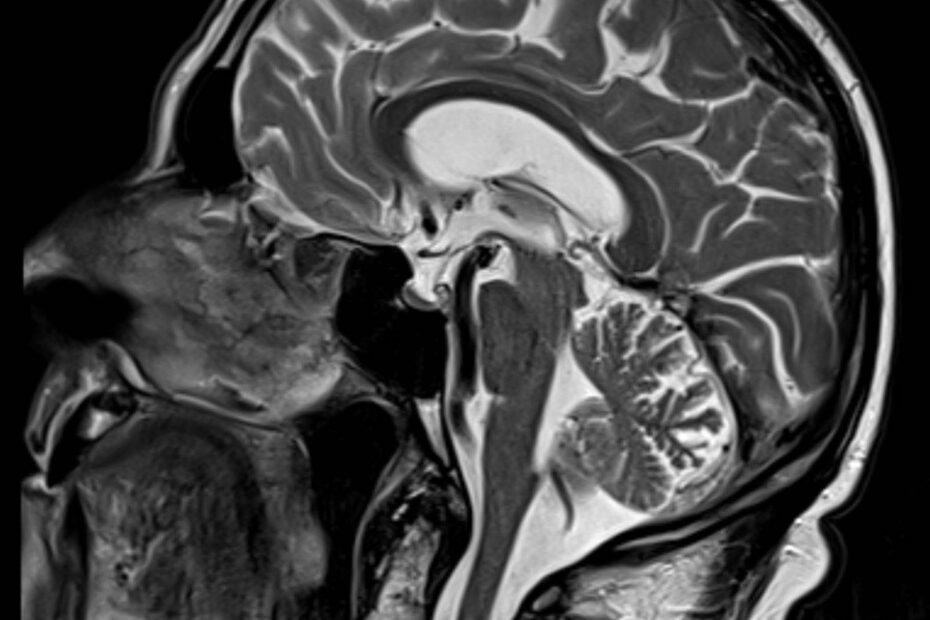

Eine Magnetresonanztomographie des Kopfes, kurz die MRT Kopf genannt, ist ein medizinisch bildgebendes Verfahren. Die MRT Kopf Untersuchung stellt mit Hilfe von Magnetfeldern und Radiowellen insbesondere unser Gehirn, Ohr, Nase und Nasennebenhöhlen, Augen, Kiefer, sowie genaue Strukturen detailliert dar. Vor allem bei diffusen oder langanhaltenden Kopfschmerzen kann eine MRT aufschlussreich sein. Vor allem ermöglicht eine … MRT Kopf weiterlesen